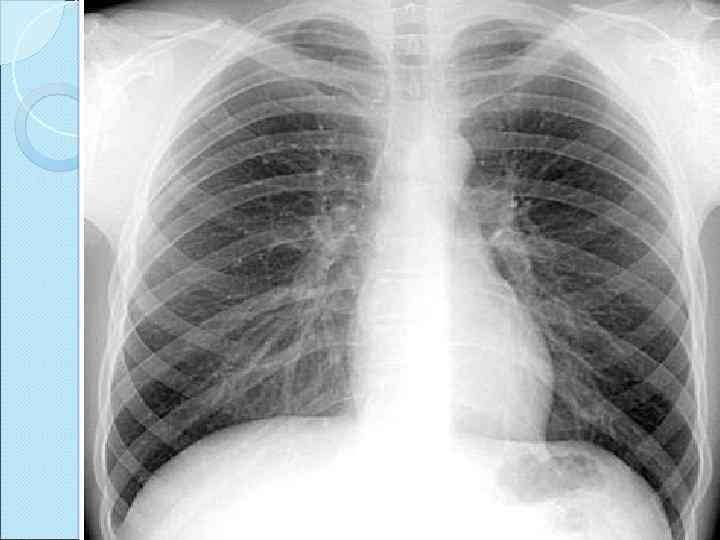

Рентген сәулесі біртекті емес ортадан өткенде, онда сәуленің жұтылуы да біртекті болмайды. Егер сәуленің таралу жолына флюоренсценттік экран қойса онда экранда бөгеттің пішініне сәйкес келетін жарықталу мен көлеңке көрінеді. Заттың құрлысын рентген сәулесімен зерттеудің негізі осы. Адам ағзасы рентген сәулесін түрліше жұтатын тіндер мен мүшелерден тұрады. Сондықтан рентген сәулесі адам ағзасынан өткенде түрліше жұтылып, экранда ішкі мүшелердің ақ-қара түсті бейнесін көруге болады

Егер адамның ағзасы қалыпты болса, онда өкпенің кескіні бірыңғай тегіс болады, ал патологиялық ауытқу болса (ісік, өкпе ауру, т. с. с. ) онда өкпе кескіні шұбарланады. Сол кескін арқылы өкпенің физиологиялық күйін анықтауға болады. Адам ағзасының физиологиялық күйін анықтауды диагностика дейді.